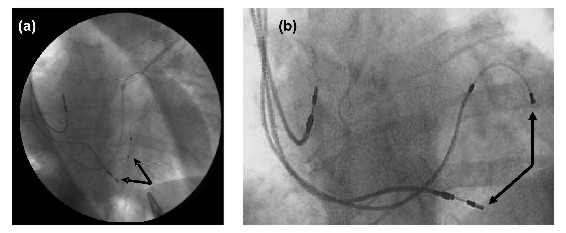

Comentarios prácticos: ¿cuándo se origina un no respondedor? (10,11). La respuesta: a) cuando se ha seleccionado mal el candidato para ese tratamiento. Pacientes en condiciones terminales, intentos de estimular en áreas inactivas, menos de 11 segmentos viables, sobre un total de 17 al ecocardiograma 3D, (especificidad 87%) (12), fenómenos isquémicos en actividad que necesitan de revascularización previa, pacientes dependientes de fármacos inotrópicos, insuficiencias mitrales orgánicas que requieren de recambio valvular, se encuentran entre las principales causas que promueven el fracaso de la CRT; b) cuando se ha realizado una técnica incorrecta. Electrodo del seno coronario en posición inadecuada, malos umbrales, distancia demasiado estrecha entre el electrodo del ventrículo derecho y el del seno coronario (figura 1), y c) programación inadecuada del resincronizador. Un intervalo AV o VV mal programado puede borrar todo el mérito de una selección e implante adecuados.

Figura 1. Pérdida del efecto de resincronización, por acentuada proximidad de los catéteres del VD y del seno coronario (a), distancia buscada (b)